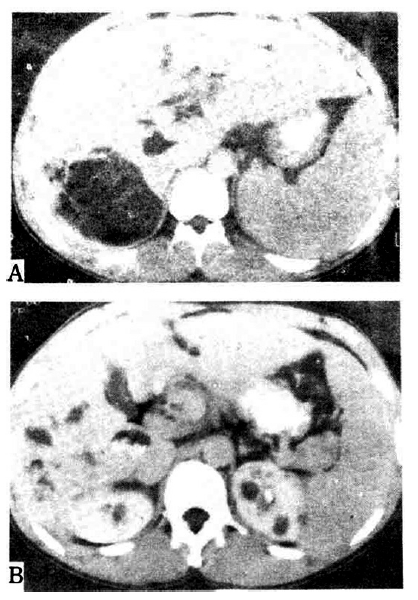

During his admission period in our hospital, massive hematemesis recurred, so he was treated by endoscopic sclerotherapy. Gastroscopic findings showed severe esophageal varix with red color sign. Abdominal computed tomography revealed Caroli’s disease, hepatomegaly with increased collateral circulation, and multiple renal cysts (Fig. 3). Portography showed multiple periportal collaterals and loss of visualization of the main portal vein. The laboratory and imaging findings are summarized in Table 1.

In our hospital, endoscopic retrograde cholangiopancreatography showed Caroli’s disease with multiple intrahepatic duct stones, while abdominal computed tomography revealed hepatosplenomegaly and multiple cysts of the liver and kidney in addition to the finding of Caroli’s disease (Fig. 4). The laboratory and imaging findings are summarized in Table 1.